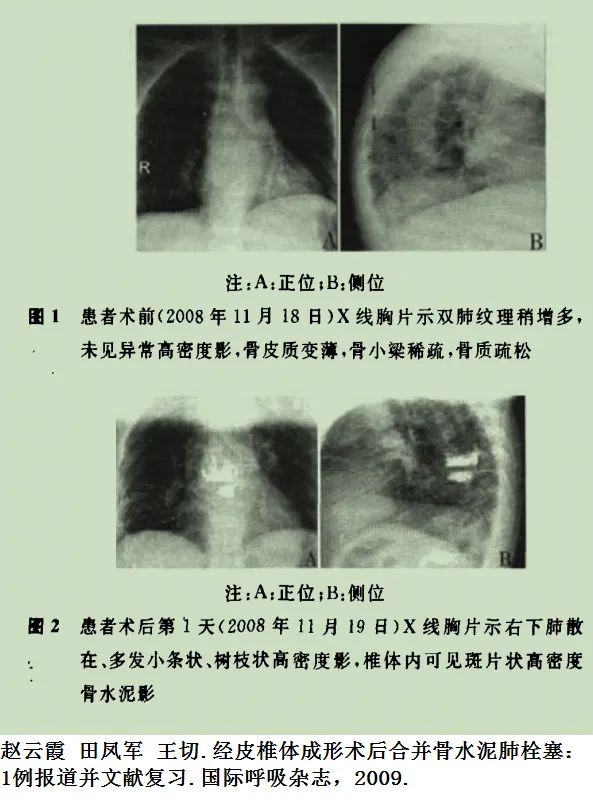

患者骨科手术后呼吸困难,急诊肺动脉CTA检查,增强CT未见充盈缺损,肺血栓形成目前不考虑。但是患者为什么出现呼吸困难,脂肪栓塞?看看CT平扫,有什么发现?乍一看,还以为是纵隔淋巴结或血管钙化,说不定还会随口给家属一句“是钙化,不用处理,没事”。结合病史,仔细一看,原来是奇葩骨水泥肺栓塞。事可大了!双肺多发的骨水泥肺栓塞。这种情况下,看增强CT,造影剂反而会掩盖肺栓塞。胸片:胸片也能诊断骨水泥肺栓塞。术前几乎都要常规做胸片,术后胸片发现新增的条状、树枝状高密度阴影,结合临床表现,也可诊断骨水泥肺栓塞。超声:心脏彩超可发现心脏内的骨水泥栓子,床旁超声也可搞定,还可以同时评价心脏功能。

肺动脉骨水泥沉积后位置、形态一般不发生变化;肺动脉走行区分支状高密度影(CT值>500HU);管腔内:高密度影直径小于近端肺动脉管腔直径;术前片对比新发实验室检查:D-二聚体、血气分析血氧饱和度、肺动脉血流动力学纤细的条纹状影,表现为肺纹理内细线纹状高密度影多位于肺野外围小动脉,分布较均匀,范围较广;节段性柱状、条状影,表现为肺纹理内呈不连续细柱状条状、枯树枝样高密度影,为肺动脉节段性完全或不完全充盈,也见于较细肺动脉分支;多发斑点状密度,肺野外围纹理内多发点状高密度影为少量骨水泥呈斑点状散在分布于小动脉所致肺栓塞并椎旁静脉渗漏。

明确经皮椎体成形术病史,术中不一定出现骨水泥渗出,可迟发临床症状,无症状至胸痛、呼吸困难、急性呼吸窘迫综合征甚至死亡。PMMA材料射线衰减强,X线平片即可发现病灶,CT平扫可进一步准确定位病灶,CTA不是必须。